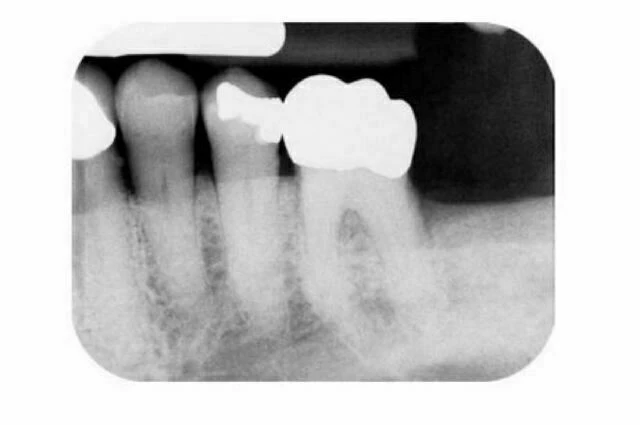

Tuy nhiên X-quang thông thường có thể không phải luôn xác định được đúng hình thái ống tủy, đặc biệt khi chỉ có một phim theo chiều ngoài trong. Trong một nghiên cứu từ 790 răng cửa và răng cối nhỏ hàm dưới được nhổ và được chụp phim X-quang để đánh giá sự phân nhánh của ống tủy trong chân răng. Khi có dấu hiệu gián đoạn một cách đột ngột của ống tủy (chẳng hạn sự biến mất đột ngột hoặc hẹp lại của một ống tủy là dấu hiệu của việc phân chia ống tủy [ví dụ sự phân nhánh]; hình 7-1), kết quả điều trị thất bại khi chẩn đoán dựa trên một phim X-quang. Vì vậy, đánh giá hệ thống ống tủy chính xác nhất khi nhà lâm sàng sử dụng thông tin từ một vài phim X-quang phối hợp với nhau cùng với việc tham dò bên trong và ngoài răng. Ngoài ra, sự phát triển gần đây của CT đã làm tăng thêm sự hiểu biết về phức hợp và mối liên hệ theo ba chiều không gian của hệ thống ống tủy.

Hình 7 – 1. Hình ảnh X-quang gốc răng cho thấy thái ống tủy chân răng. Sự biến mất bất ngờ của ống tủy chính ở răng cối nhỏ hàm dưới thường là dấu hiệu của sự phân chia ống tủy.